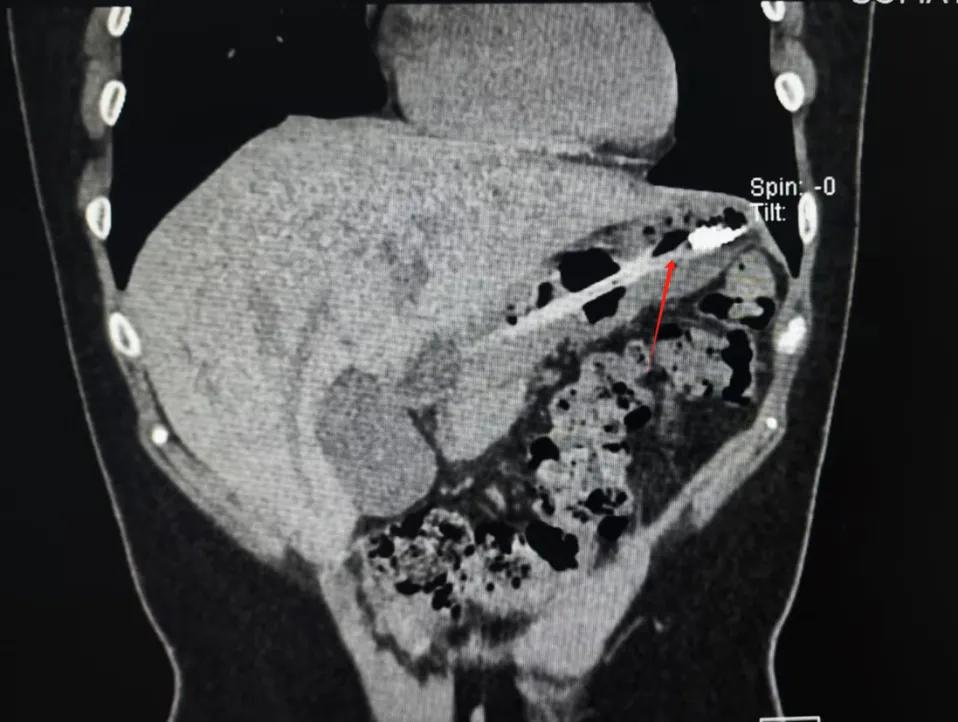

而四川成都女生小李,为了缓解因暴饮暴食带来的胃部不适和长胖焦虑,竟然选择用一次性牙刷作为催吐工具,结果手打滑,18cm长牙刷顺着咽喉直接滑了下去。

幸运的是,由于小李就医及时牙刷最终被顺利取出,并未对胃壁造成严重的损伤。